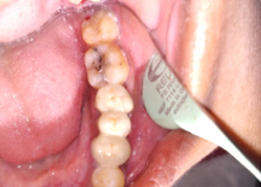

Post-OP Clinical View